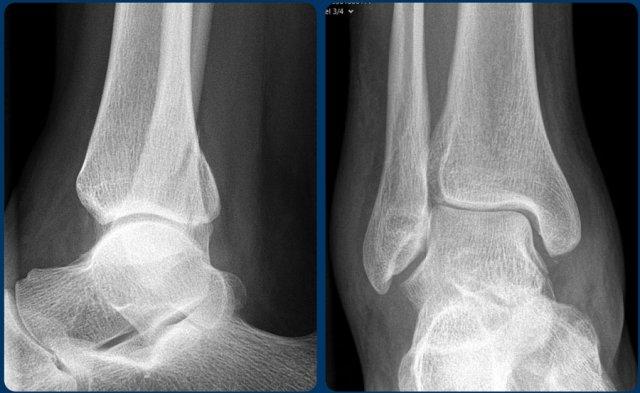

Hãy nghiên cứu các hình ảnh.

Sử dụng thuật toán và tự hỏi liệu đây là Weber A, B hay có thể là Weber C.

Sau đó xác định giai đoạn tổn thương.

Tiếp tục để xem phần thảo luận về ca lâm sàng này.

- Thoạt nhìn, có vẻ như chỉ có đơn thuần gãy mắt cá sau (tertius).

- Khi nhìn vào thuật toán, có thể thấy rằng gãy mắt cá sau có thể gặp trong gãy Weber B ở giai đoạn 3 và trong gãy Weber C ở giai đoạn 4.

Vì bệnh nhân này không có Weber B, đây phải là gãy xương Weber C. Gãy mắt cá sau đơn độc rất hiếm gặp và có lẽ không tồn tại. - Bây giờ chúng ta nhận ra phù nề phần mềm ở phía trong, đây là giai đoạn 1.

- Trên hình phóng to, chúng ta cũng nhận ra một mảnh gãy avulsion nhỏ.

Sau khi phát hiện giai đoạn 1 và 4 của cơ chế chấn thương kiểu Weber C, chúng ta có thể chắc chắn rằng cũng phải tồn tại giai đoạn 3, tức là gãy xương mác ở vị trí cao.